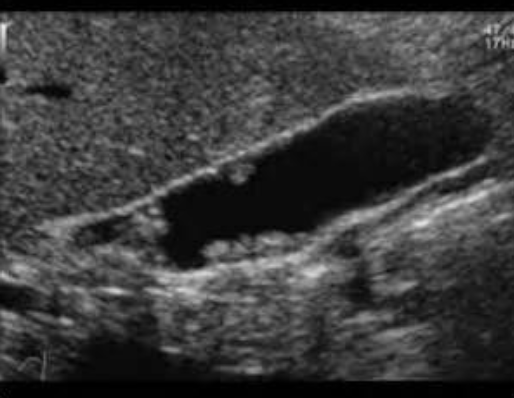

Choledocholithiasis → stones in biliary tree

clinical hx: 5 Fs → same as cholelithiasis since stone can travel

s/sx: jaundice, elevated bili and alk phos, constant RUQ pain, epigastric pain, fever, pancreatitis

2D US: “double barrel” sign, “too many tubes,” stone has rounded surface, highly echogenic, ± posterior shadowing, peripancreatic head edema/fluid → pancreatitis, gallstones, wall edema and distention

color doppler: may see twinkle artifact from stone

DDX: biliary sludge, cholangiocarcinoma